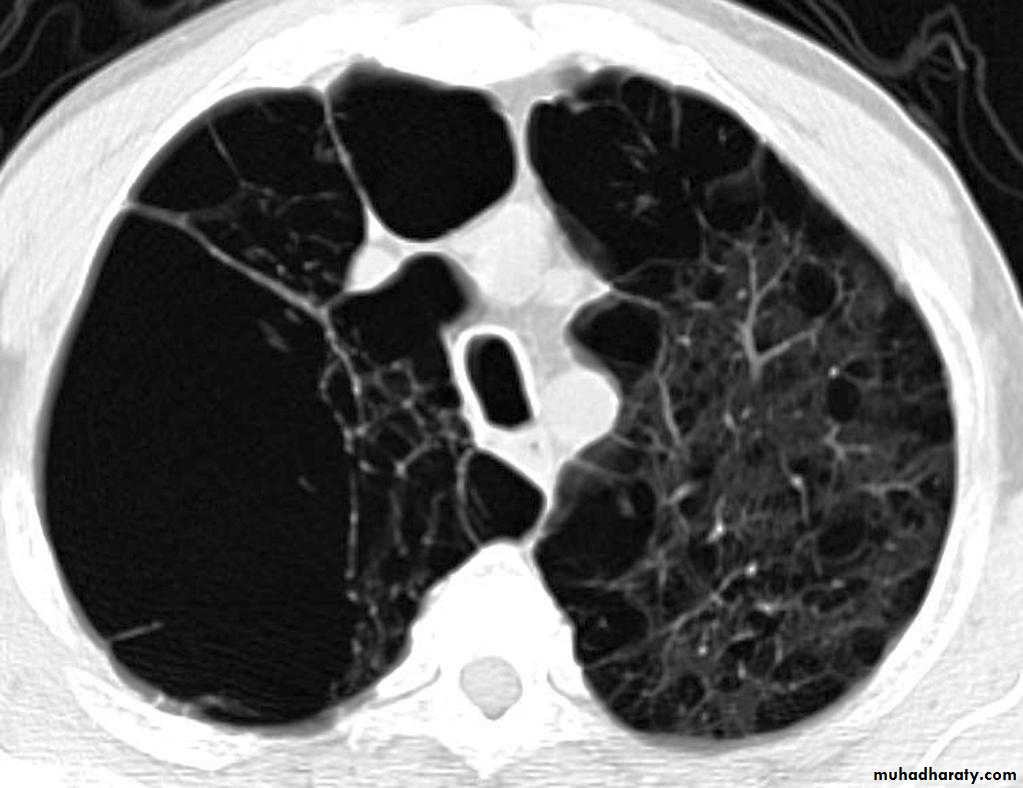

Bronchiactasis

Bronchiectasis refers to abnormal dilatation of the bronchial tree and is seen in a variety of clinical settings. CT is the most accurate modality for diagnosis. It is largely considered irreversibleCauses of bronchiactasias very important to consider

Plain radiograph

Chest x-rays are usually abnormal

1. Tram-track opacities are seen in cylindrical bronchiectasis, and

2. air-fluid levels may be seen in cystic bronchiectasis.

Honey comb shadow

3.Overall there appears to be an increase in bronchovascular markings, and bronchi seen end on may appear as ring shadows .

4.Pulmonary vasculature appears ill-defined, thought to represent peri bronchovascular fibrosis .